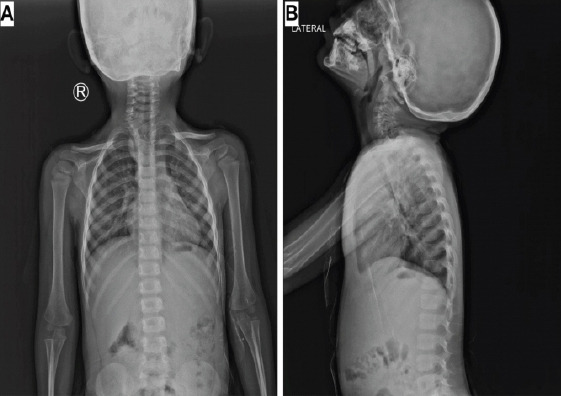

Case report: A 4-year-old boy was referred to our spine surgery unit for the evaluation and management of an incidentally detected T1 vertebral anomaly. Magnetic resonance imaging revealed the presence of a focal defect over the right half of the T1 vertebral body, through which herniation of a fluid-filled sac into the pre- and right paravertebral regions was noted. A diagnosis of anterior thoracic meningocele was made, and surgery was advised. Following surgical exposure of the entire extent of the sac, needle aspiration to decompress the lesion was performed, which yielded a milky-colored viscous fluid, unlike cerebrospinal fluid. The likelihood of an enterogenous cyst was suspected. The lesion was excised at the level of the base of its peduncle, and the vertebral defect was closed using a small contoured plate. Histopathologic evaluation confirmed the presence of an enterogenous cyst.